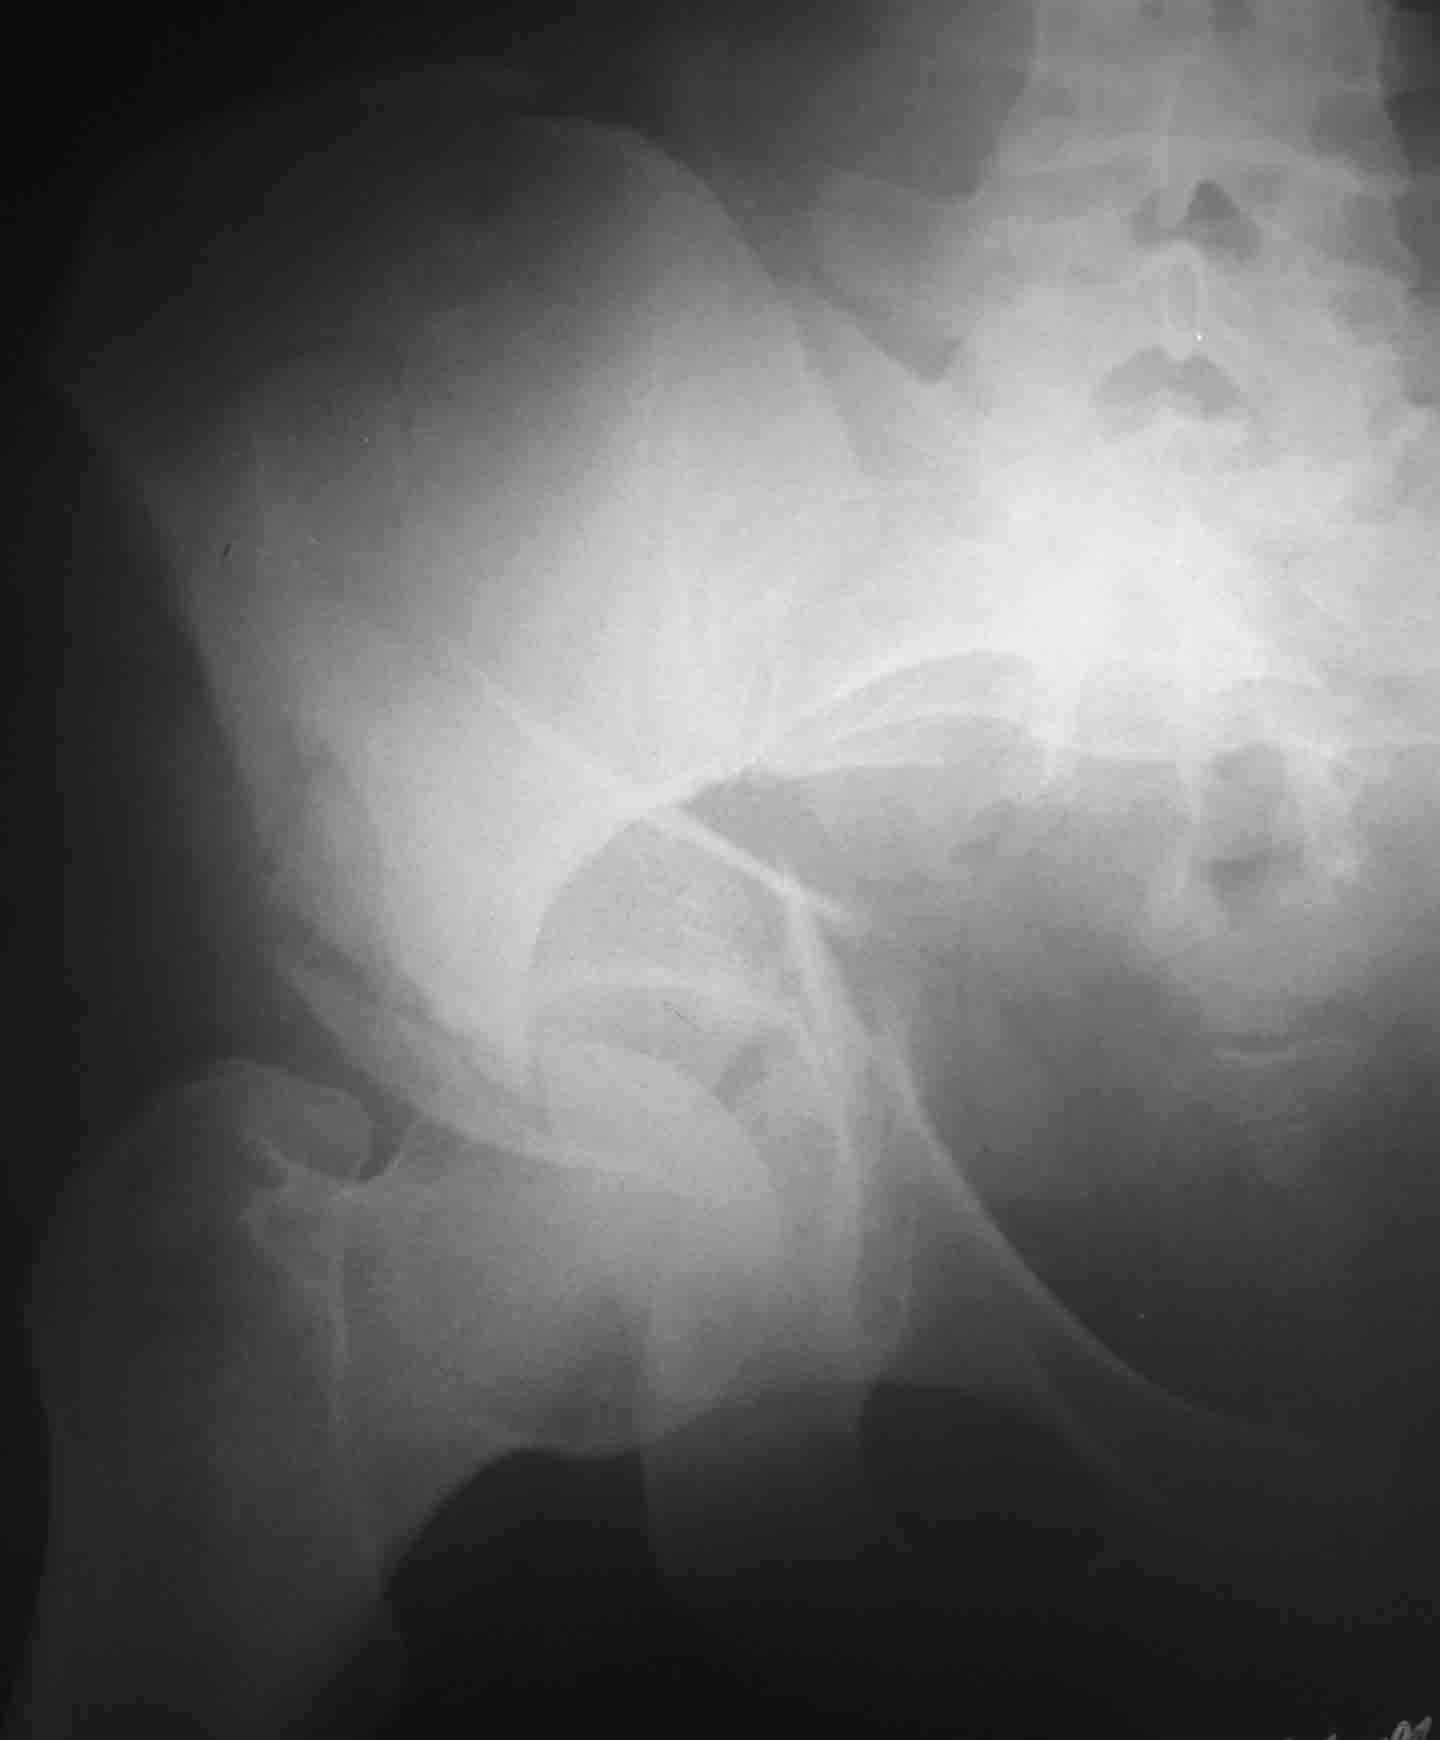

Пациентка 26 лет поступила в больницу 9 дней назад после кататравмы (падение с 4-го

этажа)Тяжелая сочетанная травма: Ушиб головного мозга средней тяжести.З/полифокальный

перелом таза (оскольчатый чрезвертлужный справа, латеральной массы крестца слева со

смещением отломков. З/оскольчатый перелом н/3 правого бедра. З/оскольчатый перелом

правой пяточной кости. Тупая травма живота - разрыв слизистой толст кишечника, кисты

яичника.

При поступлении - лапаротомия, ушивание ран кишечника, резекция кисты; скелетное

вытяжение за правую н/конечность (бугрист б/б кости) На 2-й день на таз наложен стержневой

аппарат из "того что было" (по паре стержней в подвздош кости) - естественно, при таком

Встает вопрос - что и в какой последовательности делать с

поврежденными сегментами скелета? Думали о варианте: Первым этапом -

погружной остеосинтез бедра (DCS? интерлокинг?)и ,возможно, пяточной

кости.Вторым этапом - стрежневой остеосинтез таза с бедренным модулем

(внутренний остеосинтез таза, думаю, по соматике пациентки будет

возможен не скоро)